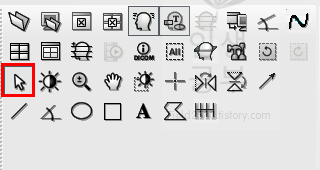

마우스 커서 모양으로 된 버튼을 클릭해 줍니다. 이 버튼은 X-ray 화면에 표시된 주석을 선택할 때 많이 사용합니다.